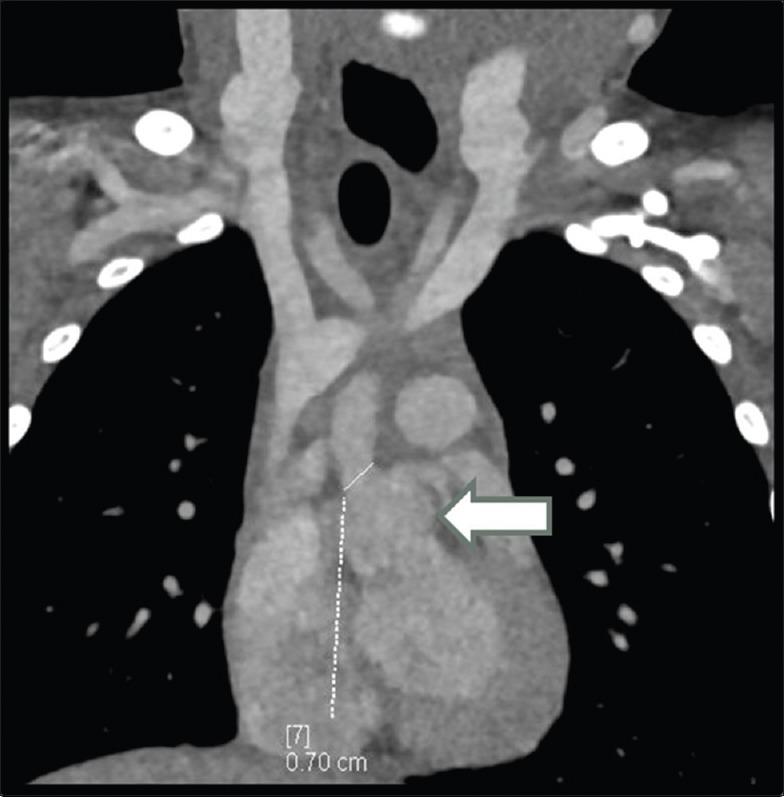

威廉姆斯-贝伦综合征是一种多系统遗传性疾病,由7号染色体长臂11.23区域的半合子缺失引起,该区域包含约28个基因,包括弹性蛋白基因ELN。心血管异常很常见,与弹性蛋白不足有关。这些异常包括70%的病例出现主动脉瓣上狭窄(SVAS)、肺动脉瓣狭窄和肾动脉狭窄。主动脉瓣上狭窄的确定性治疗包括对动脉病变进行手术矫正。SVAS手术矫正后的结果取决于动脉病变的程度和其他相关病变的存在情况。我们报告一例患有威廉姆斯-贝伦综合征并伴有SVAS的4岁男孩病例。在手术干预前,对该患者进行了计算机断层血管造影评估,以确定主动脉病变的程度。